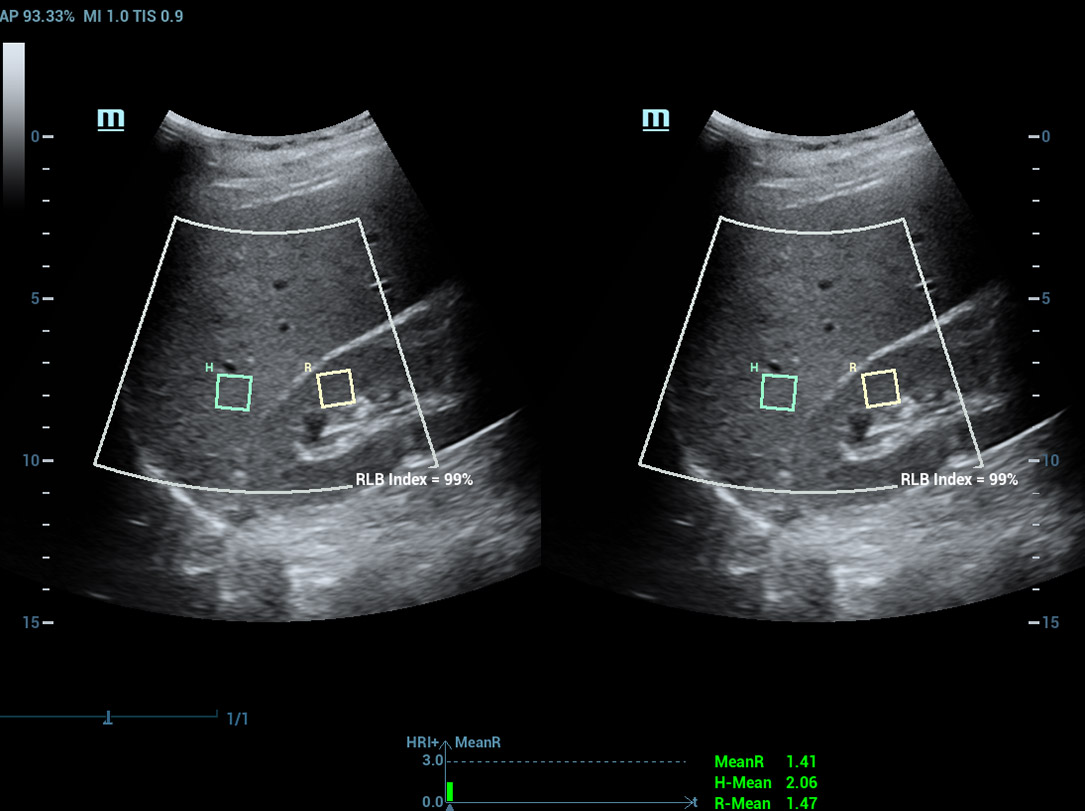

Laboratû°rio multiparamûˋtrico de fûÙgado gorduroso

Um novo salto para a pesquisa sobre esteatose

Laboratû°rio multiparamûˋtrico de fûÙgado gorduroso

O laboratû°rio multiparamûˋtrico de fûÙgado gorduroso oferece vûÀrias ferramentas de anûÀlise quantitativa baseadas em diferentes tecnologias. Permite a anûÀlise quantitativa da esteatose e melhora a sensibilidade na detec??o de fûÙgado gorduroso em estûÀgio inicial.